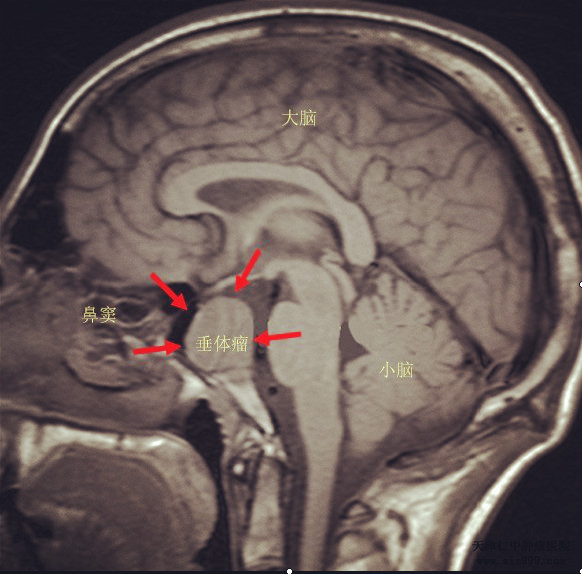

MRI影像

垂体瘤